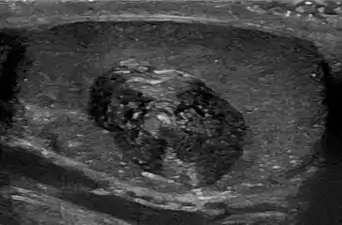

Epidermal cyst on the neck, inflamed